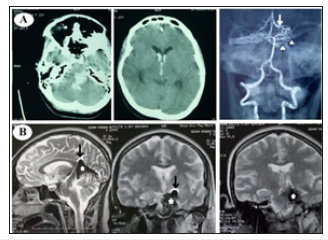

A 23 years old female without medical history presented with sudden onset of headache, vomiting with noticed difficulty to move right side of the body. By examination the patient has: neck rigidity, right sided spastic weakness (grade 2) and left sided ataxia; mRS 4. Noncontrast CT brain was done and showed hematoma in the left lateral wall of pons and midbrain; extending to the 4th, 3rd and both anterior horns of lateral ventricles. CT angiography showed cisternal AVM drained by enlarged deep vein (mostly the left basal vein of Rosenthal). MRI brain showed cisternal hematoma (ambient and quadrigeminal) elevating the tentorium (Figure 1).

Figure 1:O(A) CT brain and CT angiography showing hematoma in the left lateral pons and midbrain extending to the 4th, 3rd and anterior horns of lateral ventricles as a result of ruptured cisternal AVM that is drained by enlarged deep vein. (B) MRI brain showed hematoma in the ambient and quadrigeminal cisterns; elevating the tentorium cerebelli.